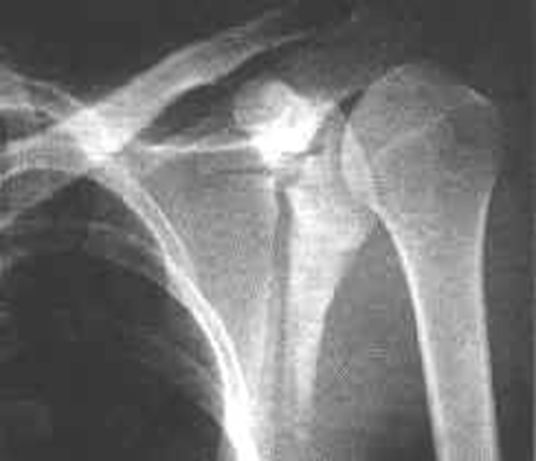

正常肩关节

锁骨骨折

常发生在中段。多为横断或斜行骨折,内侧断端受胸锁乳突肌的牵拉常向上后移位,外侧端受上肢的重力作用向内、下移位,形成凸面向上的成角、错位缩短畸形。

肩胛骨骨折

分型–肩胛骨体部骨折

常见–肩胛颈部骨折–肩胛盂骨折–喙突骨折–肩峰骨折,移位多不明显。

肩锁关节脱位

肱骨外科颈骨折

内收或外展型损伤–最常见–骨折线为横行,伸展型损伤–间接外力引起–骨折线横行,向前成角,屈曲型损伤:较少见。